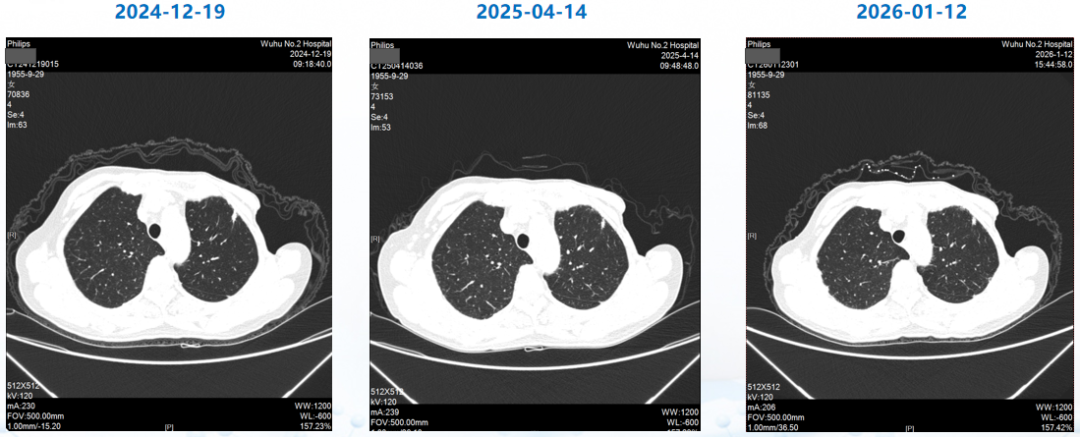

治疗3个周期后(2024-04-22),患者复查CT,肺转移灶、肝转移灶疗效评估达PR,至末次复查(2026-01-12)时评价为疾病稳定(SD),目前患者仍在继续T-DXd治疗;治疗期间未出现间质性肺病(ILD)/肺炎相关症状,甲状腺减退症状经对症处理后较前好转(促甲状腺素:4.695 mIU/L)

△患者肺转移灶影像变化